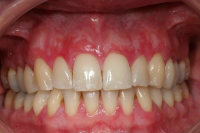

Gingival hälsa på intakt och reducerat parodontium.

Parodontal stabilitet karakteriseras av framgångsrik behandling genom kontroll av lokala och systemiska riskfaktorer, vilket resulterat i

- minimal blödning vid sondering (BVS < 10 % av tandytorna)

- fickdjup < 3 mm

- ingen progressiv parodontal nedbrytning/vävnadsförlust

- optimal förbättring i övriga kliniska parametrar hos behandlad parodontitpatient.